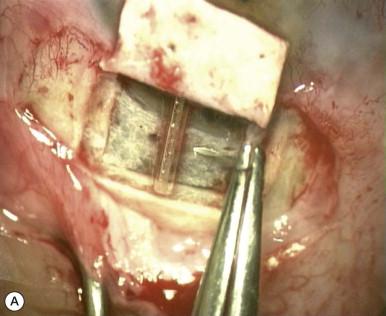

• Deep sclerectomy with external trabeculectomy may function via a variety of possible mechanisms: removal of JXT tissue; vaulting of residual trabecular meshwork toward the intrascleral cavity leading to widening of the cribriform interspaces; and development of new aqueous veins in the intrascleral space ( Fig. 96-2 ).

Figure 96-2, Implants. (A) The collagen implant was placed radially and secured with a single 10-0 nylon suture. (B) Reticulated hyaluronic acid implant. (C) Autologous scleral implant secured underneath the scleral flap. (D) Flat collagen implant.